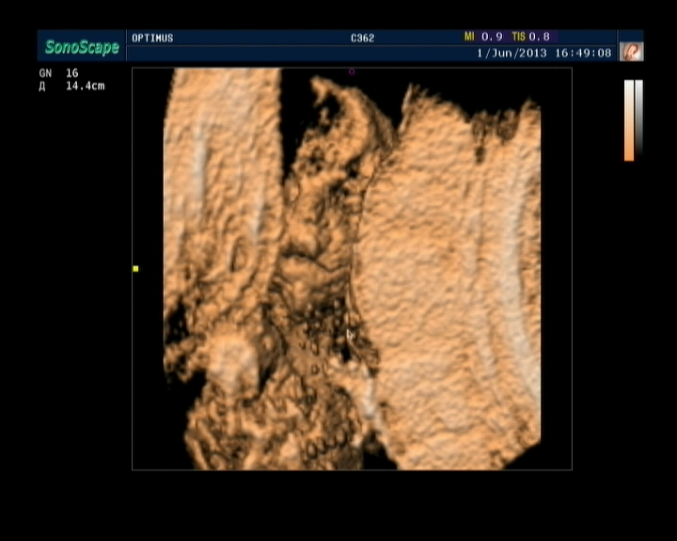

Результаты: УЗИ, КТГ, доплера, скринингаНу вот,наконец-то сходили мы на 3D УЗИ.Всё очень понравилось,делали почти час,всё рассказывали,показывали,малыш наш очень активный,постоянно барахтался,пяточку трогал,с пуповиной играл,видели как зевает,2 раза,так классно=))) Папе тоже очень понравилось=) Фото долго не получалось,да и не получилось как надо,малыш прятался=( И так,момент истины,у нас будет

Ну и вот наш сынок=))) Не знаю,разглядите или нет=)